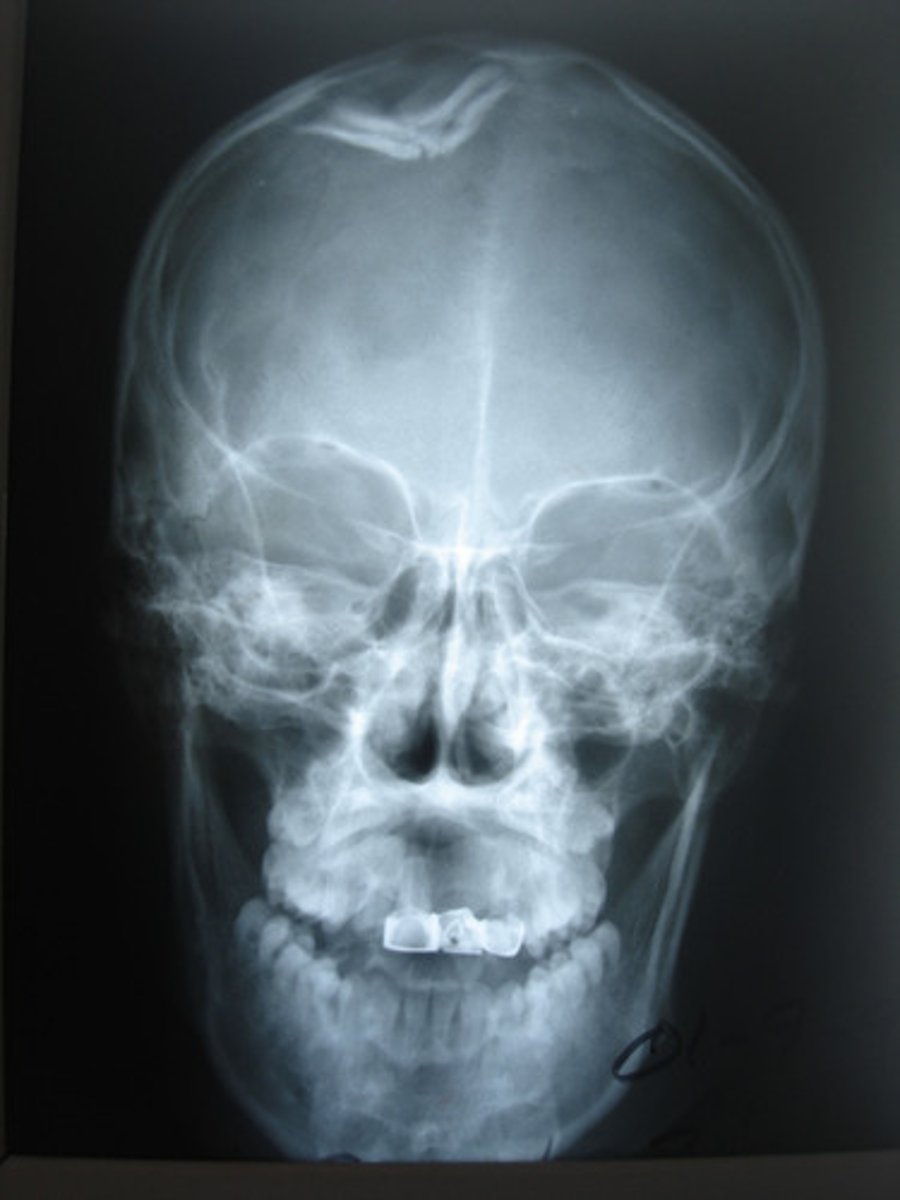

A fracture of the skull, a fragment is depressed

Depressed fx (ping-pong fx)